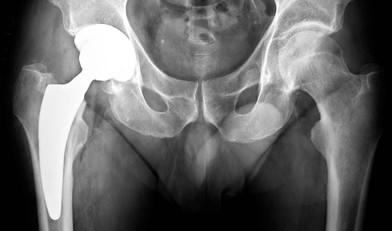

Immagine di protesi d'anca